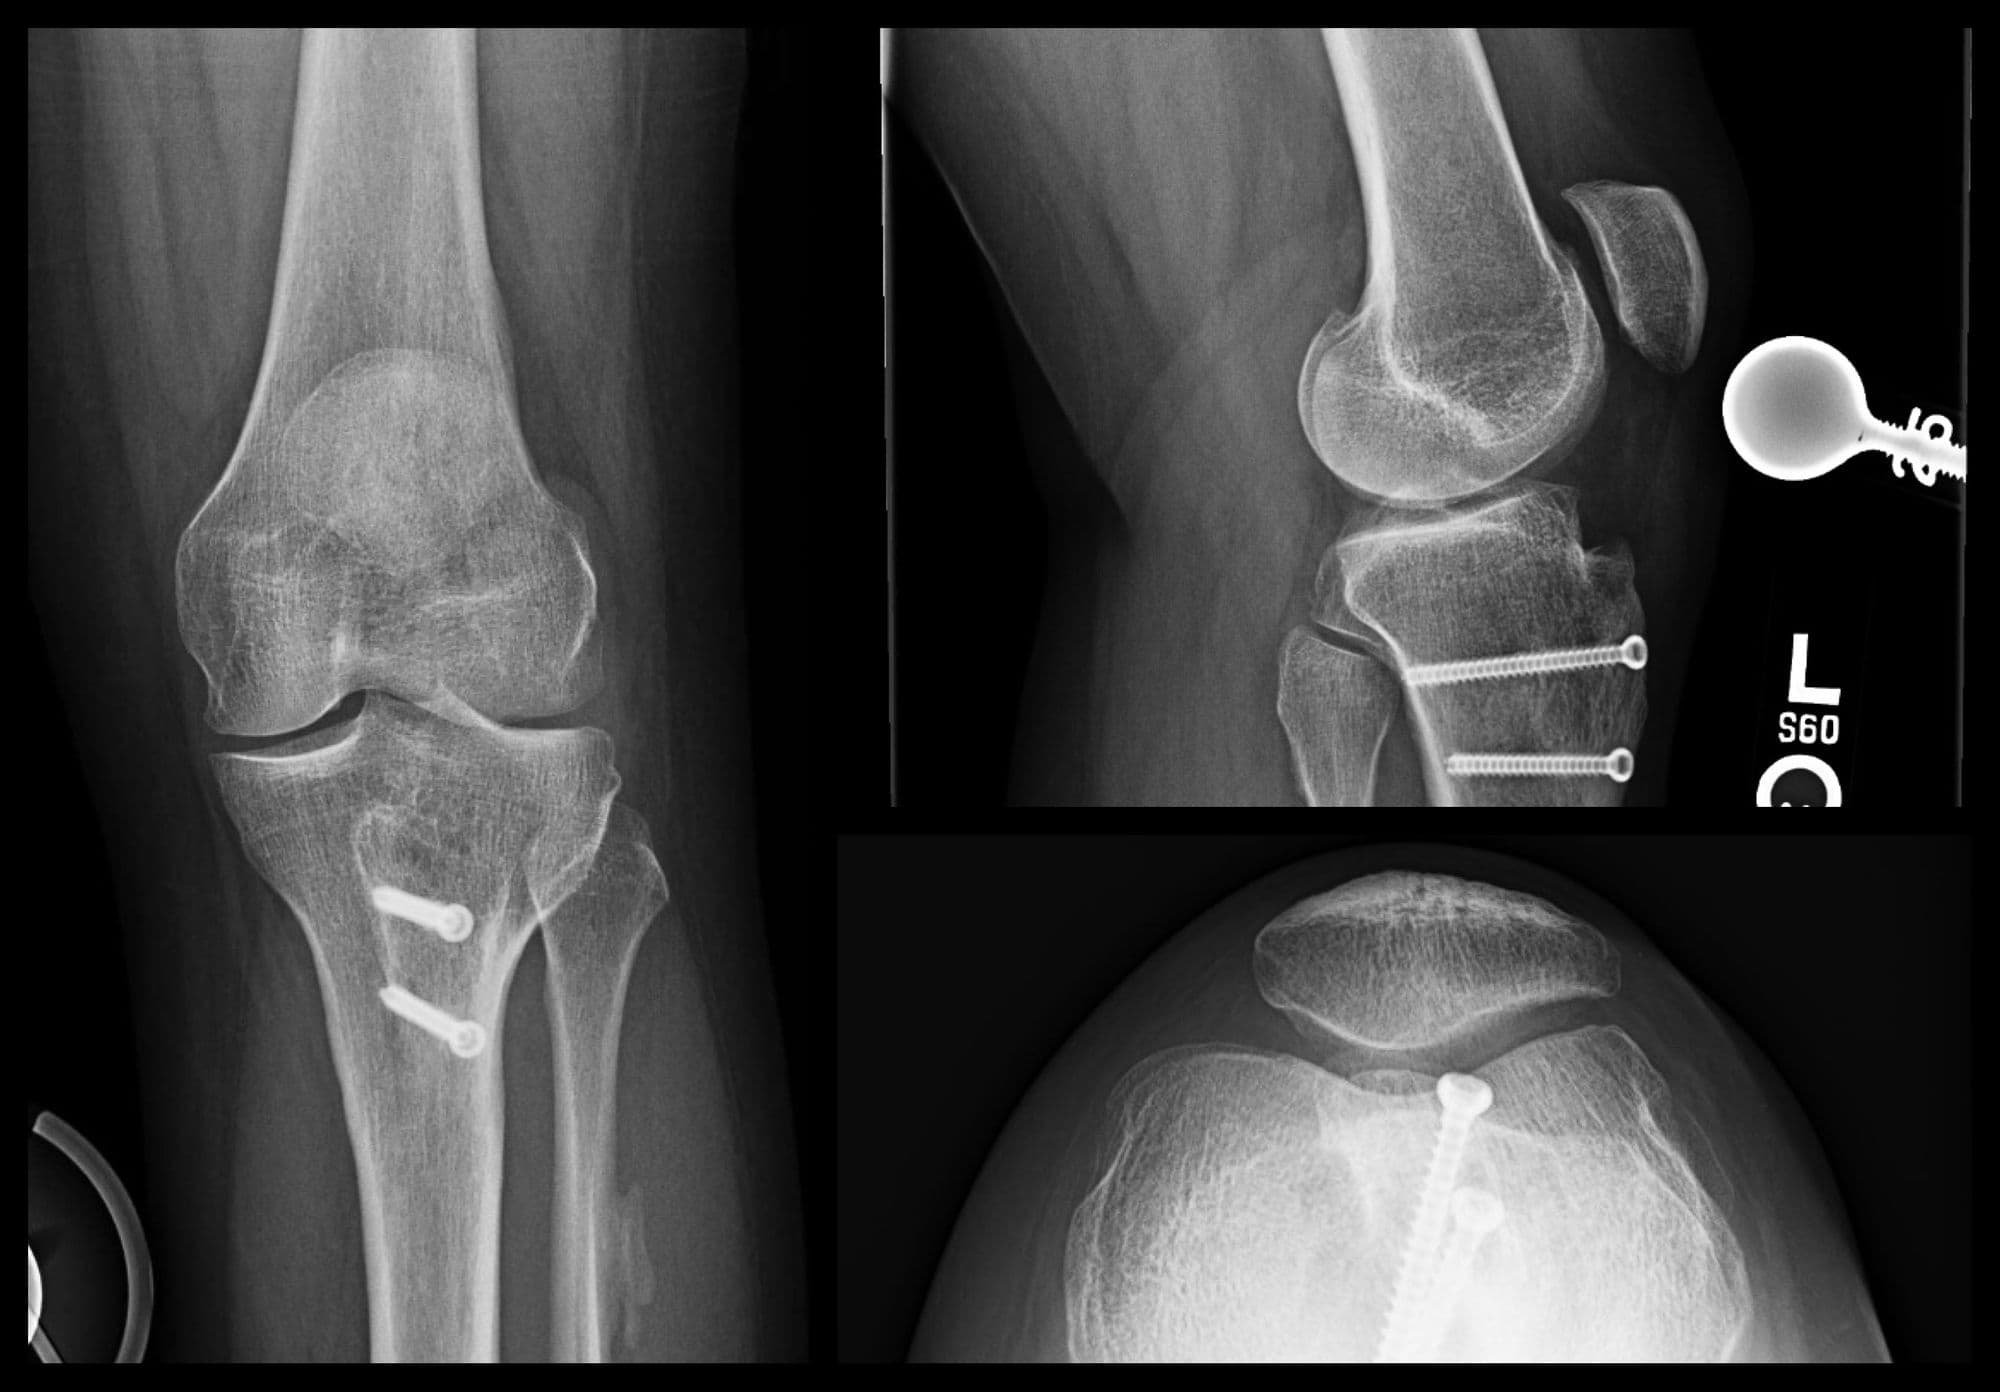

Imaging

Pre-op